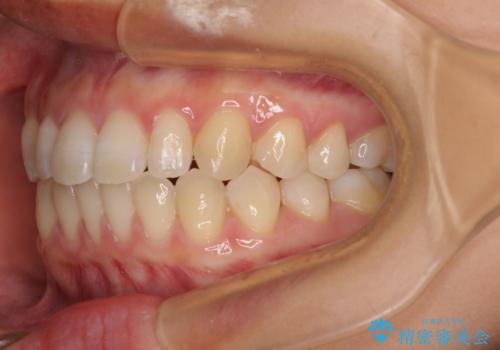

隙間だらけの歯列 インビザラインで改善

- 前歯の上下スペースと前歯の隙間を気にして来院された患者様です。

飲み込みや話をするときに舌を突出させる癖が強くあり、それが原因でスペースが空いていました。

舌癖を改善するためのトレーニングを行いながら、インビザラインにより上下の前歯の隙間を閉じていくこととしました。